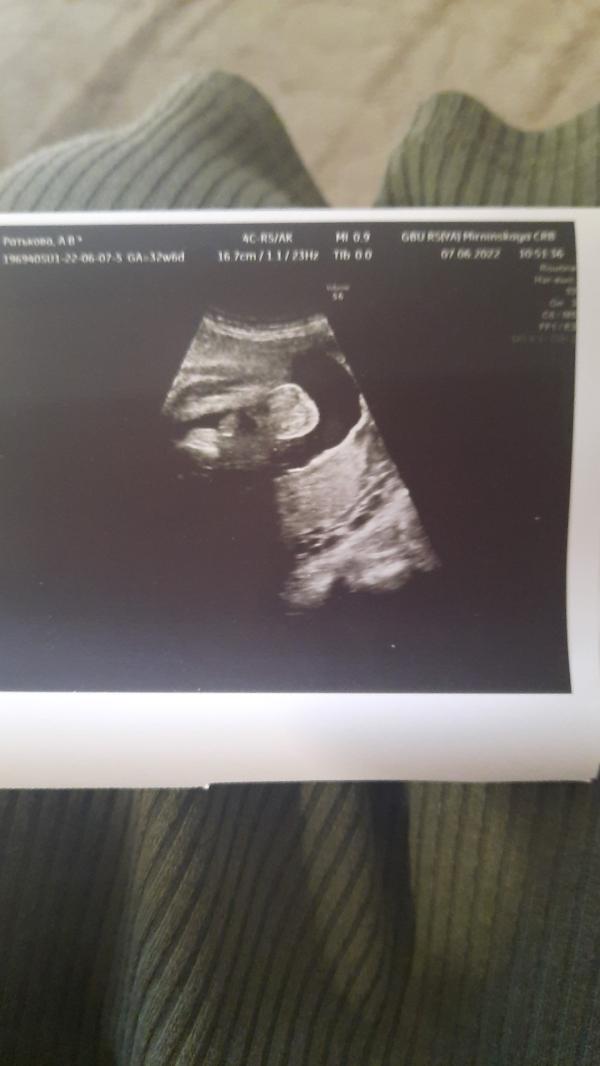

УЗИ: Срок по месячным меньше, вес 2235, мальчик подтвердился! Как выглядит малыш?

Сходила на узи. По месячным срок на 2 дня меньше. Вес 2235. Лежит правильно. Пинает сильно. Мальчик подтвердился. Очень симпатичный малыш. На первом фото кокушки, но втором очень милое личико!